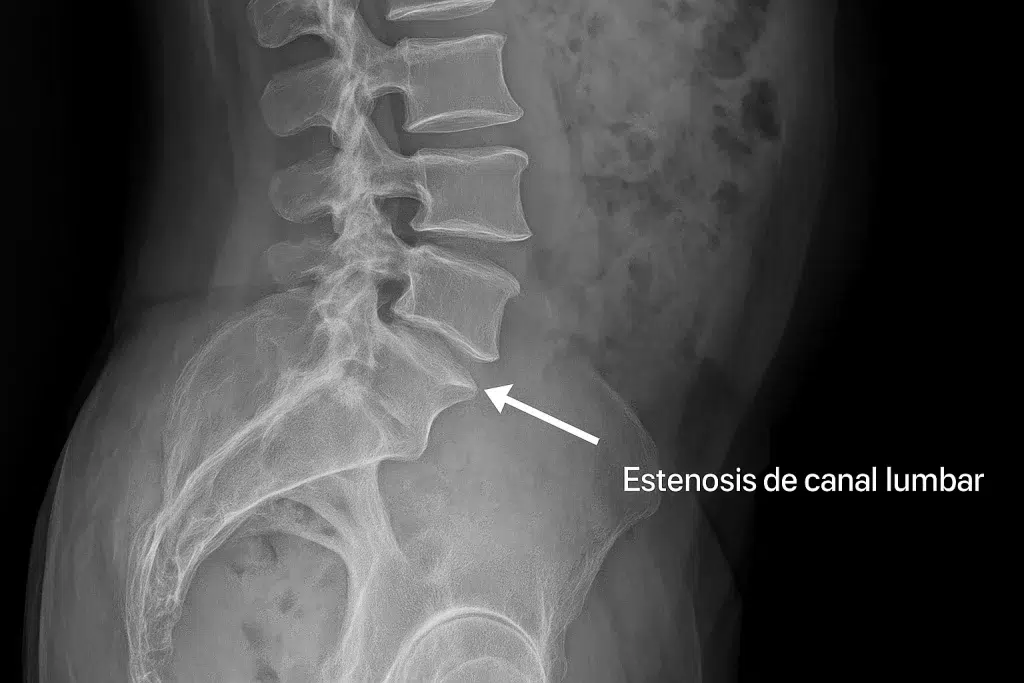

La estenosis de canal lumbar es el estrechamiento del canal por donde pasan los nervios en la zona baja de la espalda. Este estrechamiento puede comprimir las raíces nerviosas y provocar dolor, hormigueo o debilidad en las piernas.

Con la edad, los tejidos de la columna se degeneran: los discos pierden altura, los ligamentos se engrosan y las articulaciones facetarias aumentan de tamaño, reduciendo el espacio disponible para los nervios.

Por eso, la estenosis lumbar es especialmente común en personas mayores de 60 años.